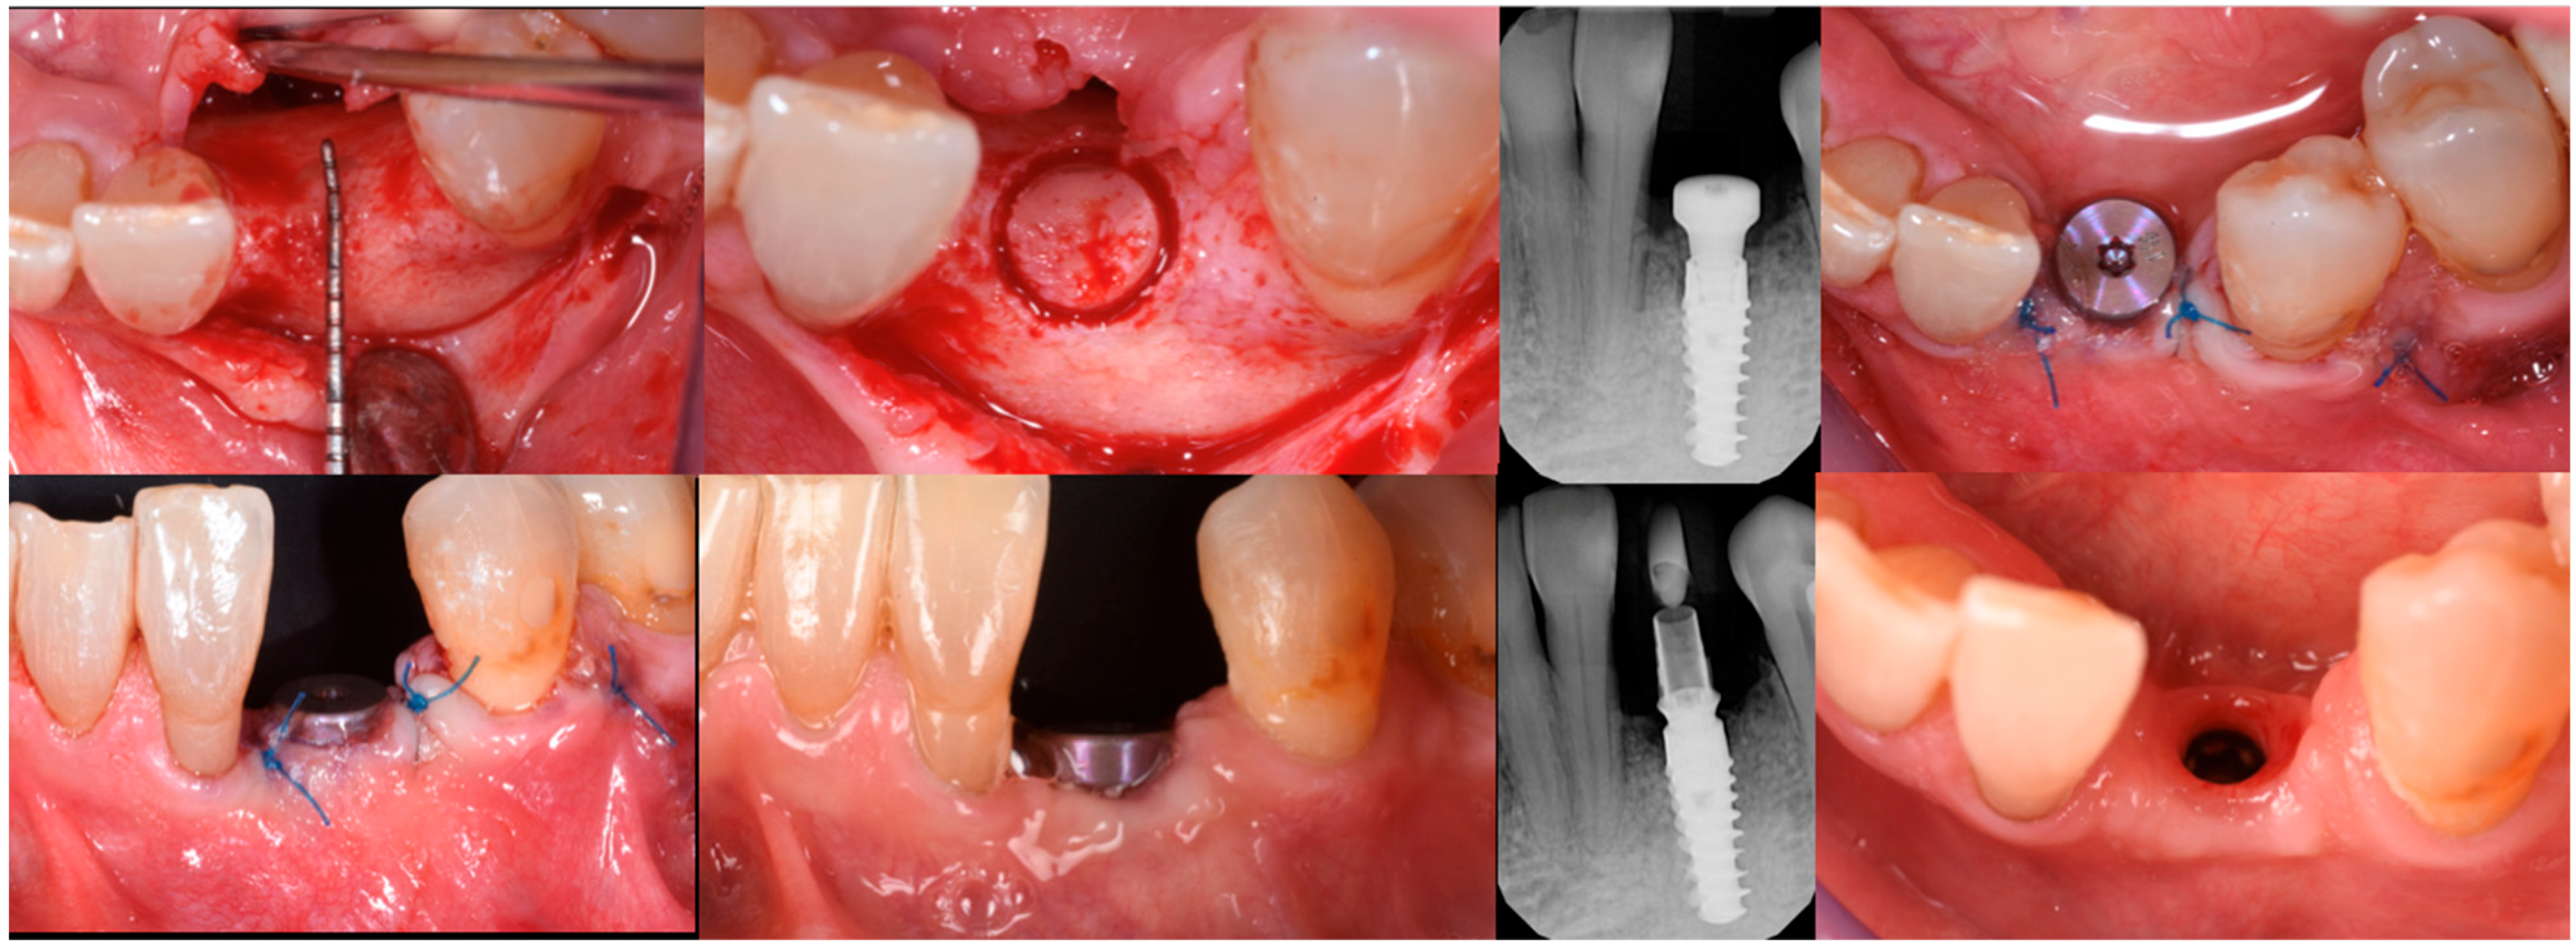

3.3. Implant Insertion and Follow-Up

On the day of surgical re-entry for implant insertion, the area was anesthetized with articaine 1:200,000, and full-thickness flaps were elevated to expose the surgical site. Clinically, newly formed bone and the two FCSs that had fully integrated into the local anatomy were observed. A trephine with a 4 mm inner diameter was used to collect a biopsy from the area for histological analysis. A 4.5 mm × 13 mm implant (Institute Straumann, Basel, Switzerland) was placed at the site. Given that the implant stability quotient (ISQ) measured above 70, a healing abutment was also placed, and the soft tissue was sutured around it. Two months post-implant placement, the healing of the soft tissues was uneventful. A temporary crown was then placed to condition the soft tissue at the site (Figure 13).

After three uneventful months, the final impression was taken, and a zirconia restoration was secured in position. The pictures and radiographs taken at the 18-month follow-up showed perfect stability of the soft and hard tissue complex (Figure 14). A summary of the procedure is provided in Figure 15a,b.

Figure 13. The sequence of biopsy, implant insertion, and healing.

Medicina 61 00683 g013